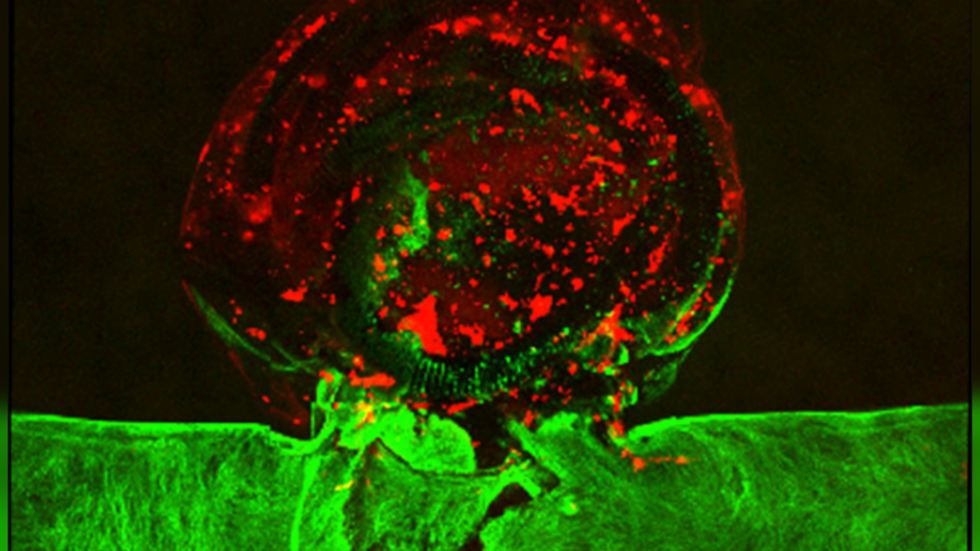

Struktura në formë aneurizmi e shtypur në 3D është bërë nga hidroxheli në të cilën futen qelizat e trurit njerëzor të quajtur hCMEC, të cilat më pas përhapen dhe veshin muret e strukturës, duke krijuar një aneurizëm ‘të gjallë’ që u lejon mjekëve të ekzaminojnë dhe të punojnë.